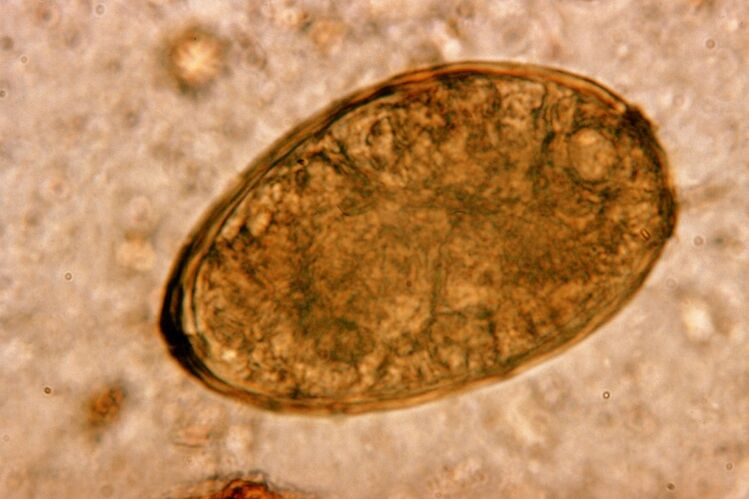

Apvaliosios kirmėlės, apvaliosios kirmėlės, gyvena ir dauginasi žarnyne. Jais užsikrečiama per kiaušinėlius, kurie į organizmą patenka su maistu arba nuo užsikrėtusio žmogaus rankų bei daiktų. Dirvožemis, vaisiai, daržovės, blogai virta mėsa ir žuvis - visa tai gali įnešti į žmogaus organizmą helmintų kiaušinius.

Verta žinoti! Apvaliosios kirmėlės sukelia sausą kosulį. Migruodami kraujotakos sistema, jų lervos patenka į kvėpavimo organus – bronchus, trachėją, plaučius – dirgindamos receptorius ir sukeldamos šį simptomą. Lervų migracijos visame kūne laikotarpis yra nuo vienos iki dviejų savaičių.

Apvaliosios kirmėlės yra labai paplitusios, todėl kosulys askaridozės fone yra tipiškas reiškinys. Apvaliosiomis kirmėlėmis užsikrečiama tradiciniais helmintozės būdais. Tai apima kontaktą su dirvožemiu, neplautų vaisių ir daržovių valgymą bei nešvarias rankas.

Ascaris lervos sukelia problemą mechaniškai veikdamos kvėpavimo sistemos audinius. Tai atsitinka parazito migracijos fazėje. Apvaliųjų kirmėlių poveikio žmogaus kvėpavimo sistemai mechanizmas ir seka yra tokia.

Patekę į virškinamąjį traktą, apvaliųjų kirmėlių kiaušinėliai, veikiami savo fermentų ir virškinimo sulčių, numeta lukštą ir virsta lervomis. Pastarieji yra apdovanoti galimybe prasiskverbti pro žarnyno sienelę į kraują. Po to jie krauju pernešami po visą kūną – pasiekia kepenis, širdį, plaučius ir kvėpavimo takus.

Ant trachėjos gleivinės yra blakstienų, kurios savo refleksiniais judesiais perneša lervą aukštyn. Tokiu atveju dirginami receptoriai ir atsiranda kosulys, į burną išmetami helmintai, iš kurių jie arba išspjaunami, arba nuryjami, grįžta į žarnyną.